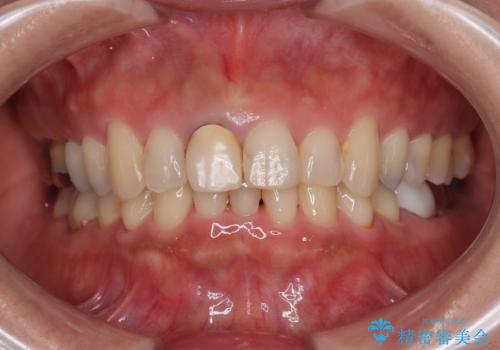

- 保険診療で装着した前歯のクラウンが変色して気になってきたとのことで来院された患者様です。

歯肉退縮による歯肉ラインの黒い縁も気になってきたとのことで、オールセラミッククラウンにて補綴治療を行うこととしました。

色がやや白いように感じますが、周りの歯をホワイトニングして白くしていくとのことで、明るめの状態での仕上がりとなりました。